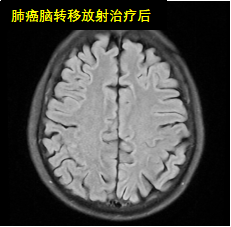

放射治療是利用高能放射線消滅腫瘤的原發灶或轉移灶的一種局部治療方法。是治療惡性腫瘤的三大手段之一,具有無創、副作用小、適應范圍廣、腫瘤局部控制率高等優點。適應癥:全身各部位早、中、晚期惡性腫瘤。